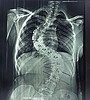

Как рассказал заведующий детским травматолого-ортопедическим отделением Центра травматологии Алексей Молчанов, пациентке диагностирован диспластический s-образный грудопоясничный сколиоз 4 степени.

Позвоночник девочки был сильно деформирован и по форме напоминал латинскую букву S. При наклоне туловища вперед в грудном отделе слева определялся пологий реберный горб высотой до 5 см. Деформация сжала левое легкое, сердце сместилось в правую сторону. Сколиоз такой тяжелой формы мог привести к необратимым последствиям для дыхательной, сердечной и других важнейших функций организма. Оперативное вмешательство было жизненно необходимо, – поделился заведующий.

До_